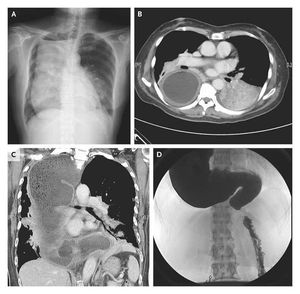

A 68-year-old woman presented with fever and dull pleuritic pain in the left chest wall. Chest radiography revealed a large mass with an air-fluid level in the right hemithorax (Panel A) and a suggestion of pneumonia in the left lower lobe. Computed tomography using contrast material revealed a severely dilated esophagus containing food, consolidation in the left lower lobe, and a compressed right lung (Panels B and C). The patient reported that she had had difficulty in swallowing food since her 20s and had adapted by eating a semiliquid diet for the past four decades. She reported often coughing when she lay in the left decubitus position. Achalasia was diagnosed by an upper gastrointestinal series (Panel D). She was successfully treated for aspiration pneumonia and was referred for further treatment of the achalasia. She declined surgical intervention as a possible means of improving the achalasia. Chi-Yen Liang, M.D. Ming-Shian Lin, M.D. Chia-Yi Christian Hospital, Chiayi City 600, Taiwan source: nejm.org